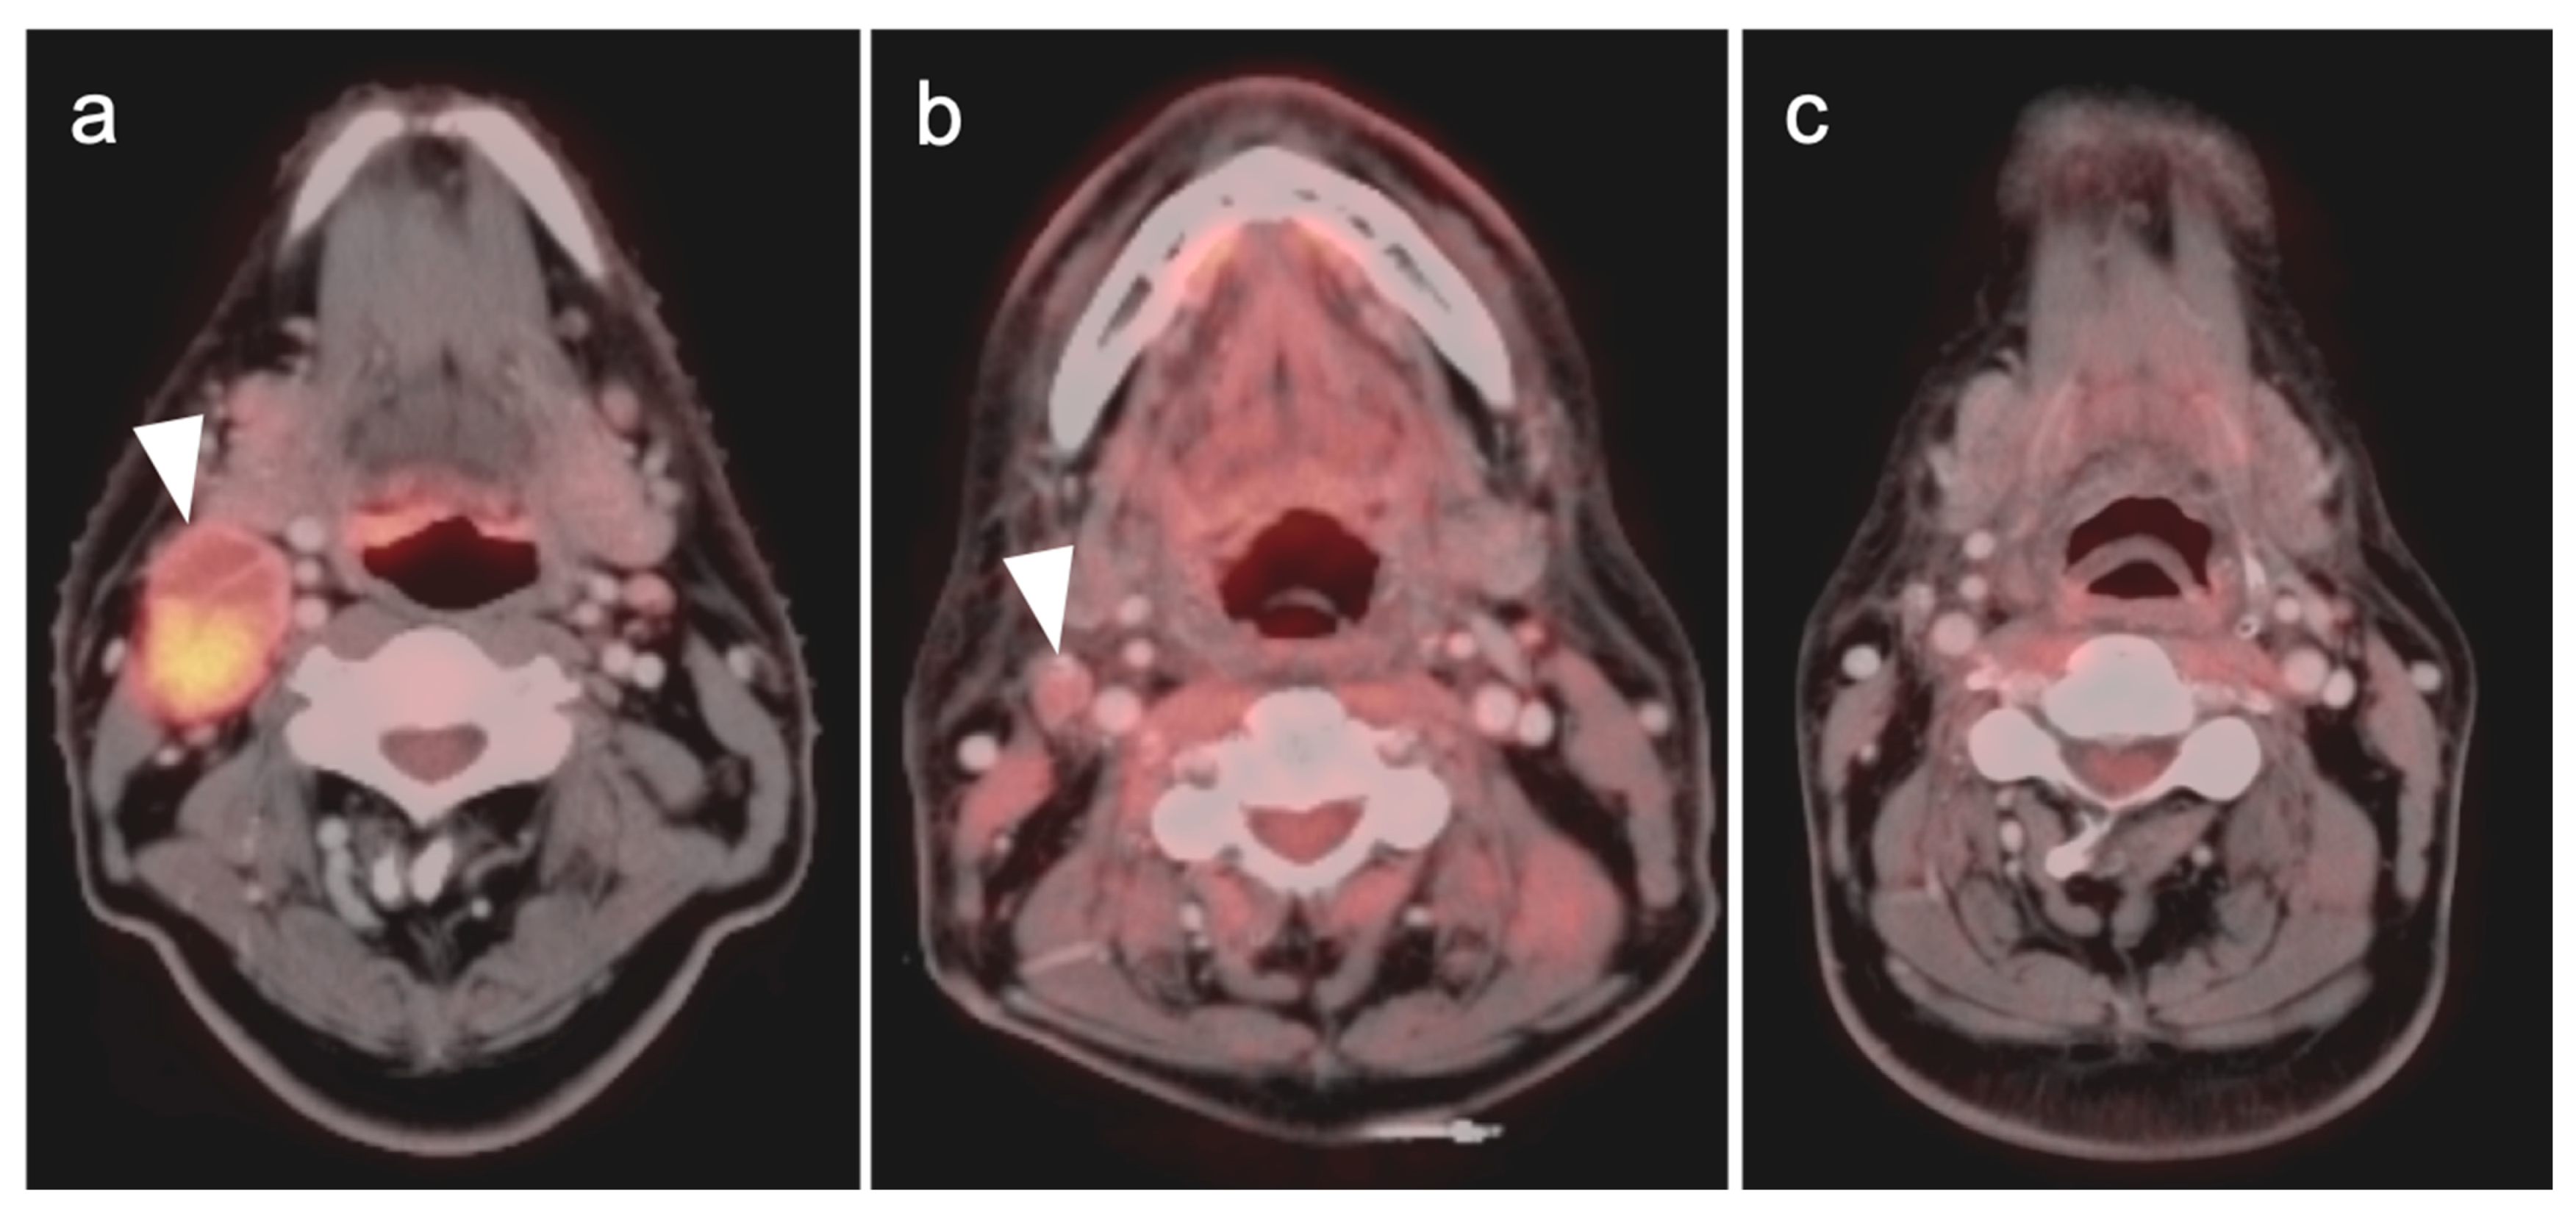

2.5. Major and Minor Salivary Gland, Lacrimal Gland Tumors

- Warthin tumor